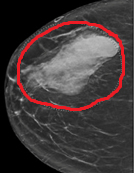

Ψηφιακή μαστογραφία. Παρουσία μάζας υψηλής πυκνότητας, ακανόνιστου σχήματος (Ευγενική παραχώρηση Dr. V. Penopoulos)